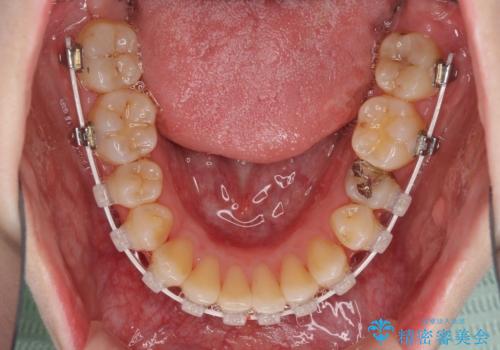

- 審美装置

治療途中で出産されたこともあり、当初予定よりも終了までに期間がかかってしまいました。

舌を前方に突出する癖があったため、上下前歯がなかなか接触しなかったことも治療期間が伸びた要因です。